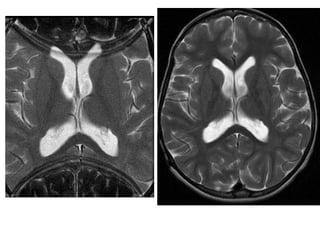

Axial T1WI of the brain at exactly the same level. Second image shows 7th and 8th cranial nerves (arrow) but the first one merely depicts them.

The reason for this is the partial volume averaging. The first slice was taken at thickness of 10 mm while second slice was taken at 3 mm.

Axial T1WI ofthe brain at exactly the same level. Second image shows 7th and 8th cranial nerves (arrow) but the first one merely depicts them. The reason for this is the partial volume averaging. The first slice was taken at thickness of 10 mm while second slice was taken at 3 mm.